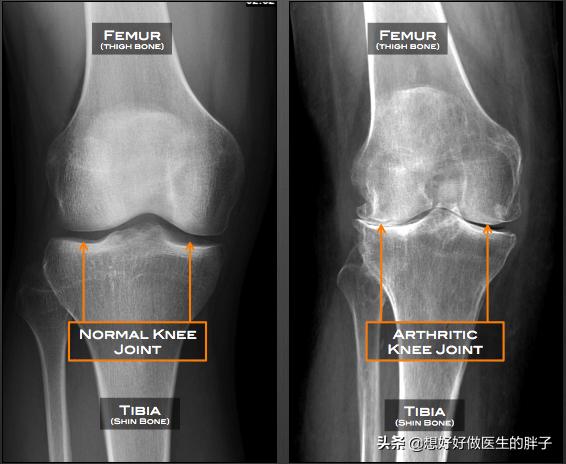

●Examen radiographique de l'articulation du genouLa radiographie du genou permet de déterminer si le patient souffre d'une ostéoporose importante et s'il y a un rétrécissement important de l'espace articulaire.l'arthroseL'existence de laPolyarthrite rhumatoïde.Ou tout autre problème de genou courant.

Comme vous pouvez le voir sur la photo ci-dessous, les articulations se sont typiquement développéesLacunes visibles, formation osseuse réduite, ostéoporose des articulations plus lourdesSi un tel patient présente des sensations et des douleurs anormales évidentes, l'injection intra-articulaire de vitrate de sodium ou l'administration constante d'analgésiques par voie orale le feront souffrir énormément, ce qui ne l'aidera pas vraiment à résoudre le problème.

L'arthrose se caractérise par les éléments suivants : elle apparaît dans les articulations portantes telles que les genoux et les hanches ; la douleur articulaire est associée à l'activité et est soulagée par le repos, et après une longue période de repos des articulations, il y a une raideur temporaire et une durée localisée. Dans les cas graves, les douleurs articulaires et la limitation des mouvements surviennent même au repos. Les articulations touchées sont souvent accompagnées d'une sensibilité, d'une hypertrophie osseuse, d'un frottement osseux et, chez quelques patients, d'une déformation. Cette maladie n'apparaît pas seulement dans une partie, l'ensemble des articulations du corps sont susceptibles de souffrir d'arthrite.

Si vous avez froid aux genoux, il peut s'agir de "vieilles jambes froides" ; si vous ressentez une douleur au genou, il peut s'agir d'arthrite ; si l'étirement du genou est sonore, il peut s'agir d'une blessure au genou. Lorsque ces trois situations se produisent en même temps, les personnes d'âge moyen et les personnes âgées doivent redoubler de vigilance à l'égard de l'arthrose du genou, qui est souvent désignée par l'expression "changements dégénératifs dans l'articulation du genou".

- "Fausses vieilles jambes" - arthrose du genou.Les personnes âgées souffrent souvent de genoux et d'os froids, de douleurs, si bien que l'on parle souvent de "vieilles jambes froides", qui sont de "fausses vieilles jambes froides", la cause la plus fréquente étant l'arthrose du genou, le patient étant stimulé par le froid et l'humidité et déclenché par la douleur ou les douleurs. Aggravation.

- fricatif--Lorsque le cartilage articulaire est très usé, les extrémités des os sous-chondraux perdent la protection du cartilage et le frottement direct émet un bruit de frottement faible et rauque ; les débris de cartilage qui se promènent dans la cavité articulaire provoquent aussi facilement des blocages, ce qui donne lieu à un bruit de frottement articulaire. Les patients doivent faire la distinction avec le claquement physiologique normal, les critères de jugement sont très simples, le claquement pathologique est souvent accompagné de symptômes d'inconfort articulaire.